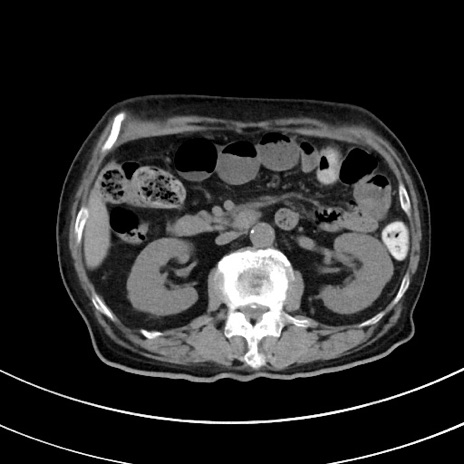

症例33(横断像)

【症例】70歳代 女性

【主訴】心窩部痛

【現病歴】延髄病変の精査・加療にて神経内科入院中。本日より心窩部痛あり。

【身体所見】右下腹部を中心に圧痛と反跳痛あり。